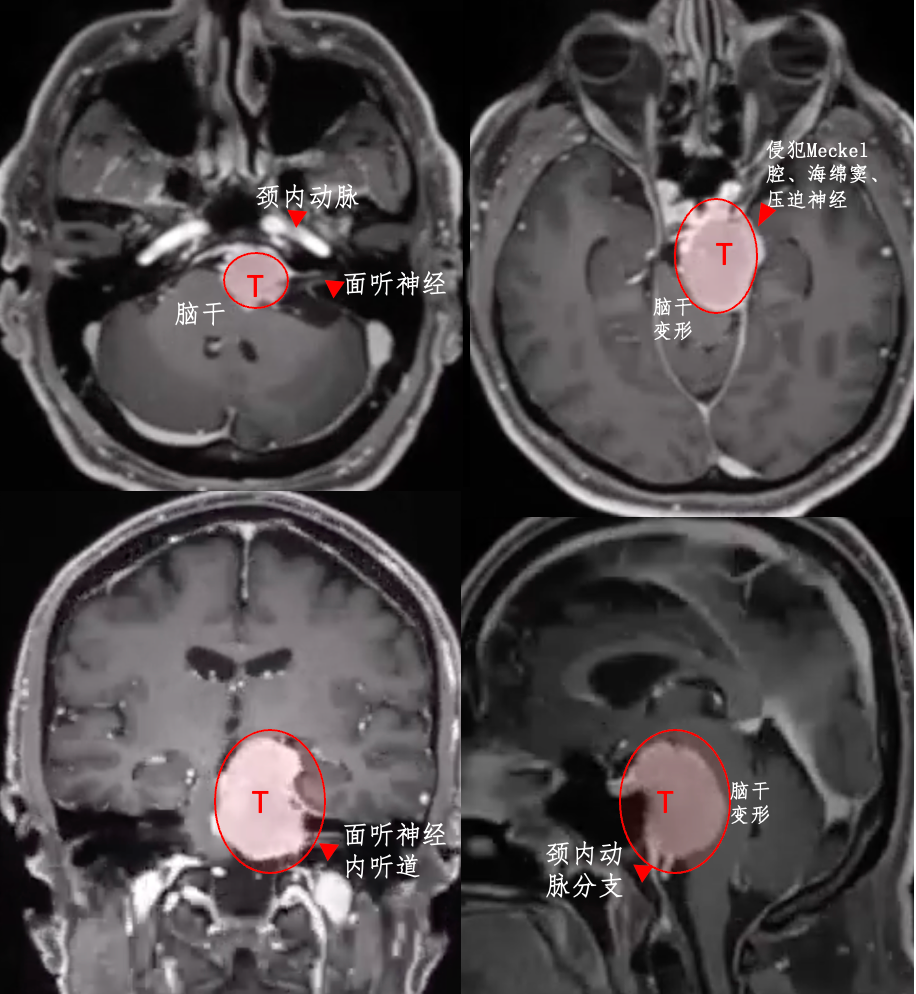

1.脑膜瘤:约1%颅内脑膜瘤起源于岩斜区,是岩斜区常见病变。它向上可侵犯岩骨尖、小脑幕、Meckel腔、鞍旁和海绵窦;向下侵犯内听道和颈静脉孔;向内侧达脑干和椎基底动脉。当肿瘤很大时,可包绕同侧Ⅲ~Ⅺ脑神经。患者临床可表现头痛、复杂的脑神经麻痹、共济失调等症状,严重者表现为偏瘫、认知功能障碍。目前,仍以手术切除为首选治疗方式。

因涉及脑干、颅神经、椎基动脉和脑底动脉环、脑室通路以及鞍区、松果体区、岩骨-斜坡区、枕大孔区、桥脑小脑角区、颈静脉孔区等脑的重要结构或功能区,关系到病人的生命、神经、内分泌调节和传导等重要神经功能,任何一处的手术损伤,都可能引起重大的神经功能障碍。并且,此类病变多处于脑或烦底深部,手术显露困难,因而既要切除肿瘤,又要最大限度地避免损伤脑干、颅神经、重要血管等临近的脑重要结构。

岩斜区脑膜瘤手术技术非常关键,需要熟悉岩斜区解剖关系并有丰富的显微操作经验。在术前放置腰穿引流,或术中甘露醇应用可明显降低脑组织压力,减少牵拉造成的副损伤。提前对脑膜瘤基底的处理可有效避免肿瘤持续出血造成的蛛网膜界面消失。肿瘤的生长将神经、血管拉伸或包绕,尤其是复发的肿瘤,会破坏蛛网膜界面,侵犯脑干软脑膜。手术时应仔细分辨和保护。肿瘤囊壁与神经、血管外膜和脑干粘连,不应勉强分离,以保护下方结构。